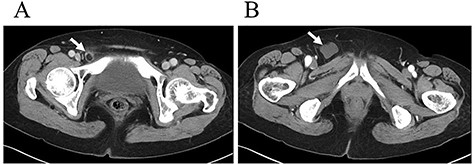

A 62-year-old woman visited our hospital with a 1-day history of lower abdominal pain and bulging from a right groin lesion. Her physical examination showed a right inguinal bulge and pain. Her abdomen was not distended and was without rebound tenderness and muscular defense. However, the bulge in the right groin lesion could not be reduced manually. Contrast-enhanced computed tomography showed a hypodense rounded lesion medial to the right femoral vessels (Fig. 1A) with fluid collection (Fig. 1B), with no intestinal obstruction or ischemia. Based on these physical and radiological findings, the patient was diagnosed as having a right incarcerated femoral hernia containing fat tissue. As there were no clear findings of intestinal obstruction, elective TEP repair was performed 1 day after admission following preoperative evaluation of her general condition. An infra-umbilical incision was made under general anesthesia. The preperitoneal space was created with blunt dissection with the aid of CO2 gas insufflation to a pressure of 12 mmHg. Two 5-mm trocars were inserted into the left mid-abdomen. The hernia sac had herniated into the right femoral canal (Fig. 2A). Therefore, we diagnosed a right incarcerated femoral hernia containing greater omentum. However, there were no findings of abscess formation or small bowel necrosis. We were able to release the hernia sac using laparoscopic forceps (Fig. 2B). After reduction of the hernia sac, 10.3 × 15.7 cm polypropylene mesh was placed in the preperitoneal space and fixed to Cooper’s ligament with a fixation device (ProTack™, COVIDIEN) (Fig. 3). Intraperitoneal observation was not performed because we considered it unnecessary to confirm the presence of intestinal damage. The patient’s postoperative course was uneventful, and she was discharged from our hospital 3 days after surgery. Presently, at 1 month after surgery, the patient is doing well without recurrence or mesh infection.

Contrast-enhanced computed tomography showed a hypodense rounded lesion (A, arrow) medial to the right femoral vessels with fluid collection (B, arrow).